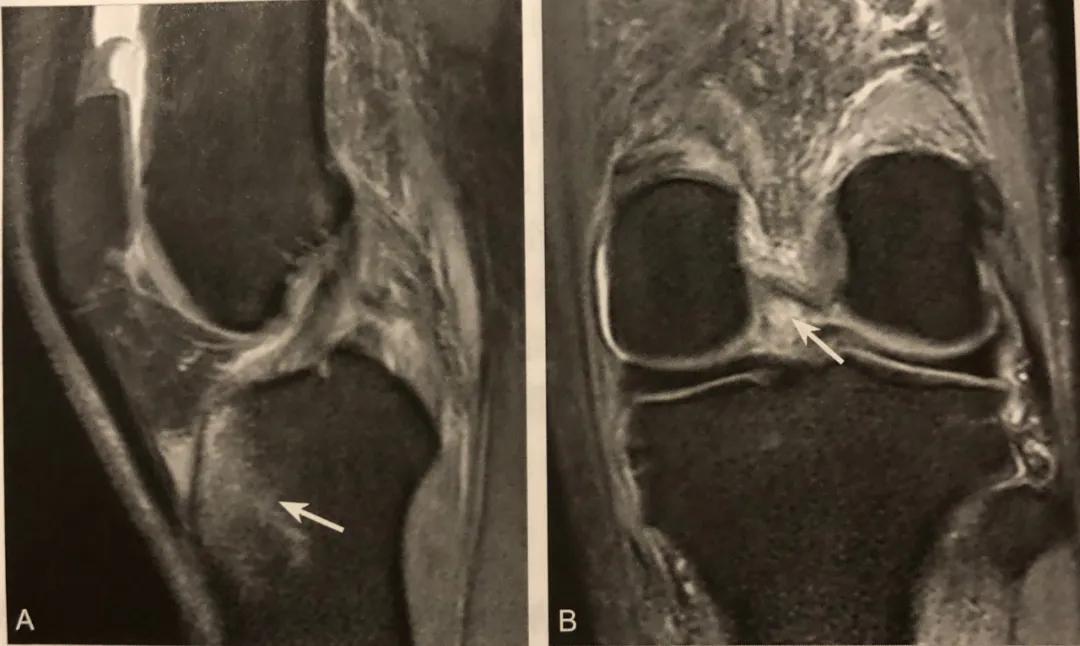

侧囊征/ Segond 骨折

A. 膝关节 ⅹ 线前后位片,胫骨平台外侧缘撕脱椭圆形小碎骨片,长轴平行于胫骨,见侧囊征;

B. 同一患者 MRI 冠状位 PDWI SPAIR 显示胫骨平台外侧缘撕脱骨折,内外侧半月板内横形高信号,提示损伤(粗箭头);

C. 矢状位 PDWI SPAIR 中间层面 PCL 显示肿胀,信号不均,提示 PCL 水肿,呈轻度损伤

侧囊征在膝关节 x 线前后位或 CT、MRI 冠状位显示,表现为胫骨平台外侧缘撕脱椭圆形小碎骨片,长轴平行于胫骨。

CT 可显示多数碎骨片向外移位,股骨内外侧髁和胫骨后缘骨折;MRI 可观察膝关节韧带和半月板损伤情况,韧带和半月板可呈轻度水肿、部分撕裂和完全撕裂,T2WI 信号增高,关节面下常见骨挫伤表现。

阅片要点:

1. 在膝关节 Ⅹ 线前后位片或 CT、MRI 冠状位观察;

2. X 线片或 CT 观察到侧囊征( Segond骨折),应该建议 MRI 检查;

3. Segond 骨折是 PF-ITB 和 ALL 胫骨附着点撕脱骨折的直接征象;

4. Segond 骨折和 ACL 断裂具有高度相关性,但无直接关系;

5. 无 ACL 损伤的 Segond 骨折,MRI 需注意观察其他韧带、半月板及骨质损伤;

6. MRI 注意观察伴发的关节面下对吻性骨挫伤表现。